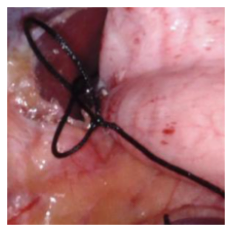

Endoscopic video recordings are widely used in minimally invasive robot-assisted surgery, but when the endoscope is outside the patient's body, it can capture irrelevant segments that may contain sensitive information. To address this, we propose a framework that accurately detects out-of-body frames in surgical videos by leveraging self-supervision with minimal data labels. We use a massive amount of unlabeled endoscopic images to learn meaningful representations in a self-supervised manner. Our approach, which involves pre-training on an auxiliary task and fine-tuning with limited supervision, outperforms previous methods for detecting out-of-body frames in surgical videos captured from da Vinci X and Xi surgical systems. The average F1 scores range from 96.00 to 98.02. Remarkably, using only 5% of the training labels, our approach still maintains an average F1 score performance above 97, outperforming fully-supervised methods with 95% fewer labels. These results demonstrate the potential of our framework to facilitate the safe handling of surgical video recordings and enhance data privacy protection in minimally invasive surgery.